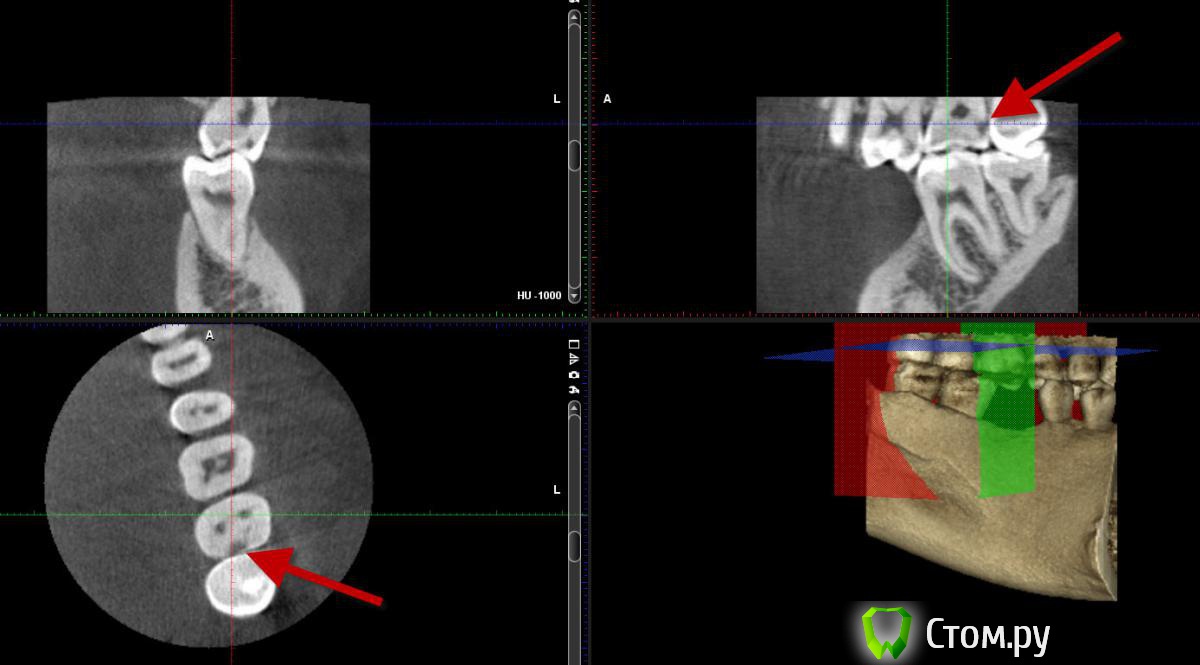

bobrdobr Опубликовано 17 февраля, 2014 Автор Поделиться Опубликовано 17 февраля, 2014 Еще вопрос, пожалуйста. Сделал КТ для имплантации. На верхнем зубе в двух проекциях вижу затемнение на контактной поверхности (отметил стрелкой). На панорамнике тоже можно увидеть. Возможен кариес? Ссылка на комментарий

IvanK Опубликовано 17 февраля, 2014 Поделиться Опубликовано 17 февраля, 2014 надо лечить Ссылка на комментарий

red_butler Опубликовано 18 февраля, 2014 Поделиться Опубликовано 18 февраля, 2014 + 1 лечить, кариес это. Покажите срезы гайморовой пазухи слева Ссылка на комментарий